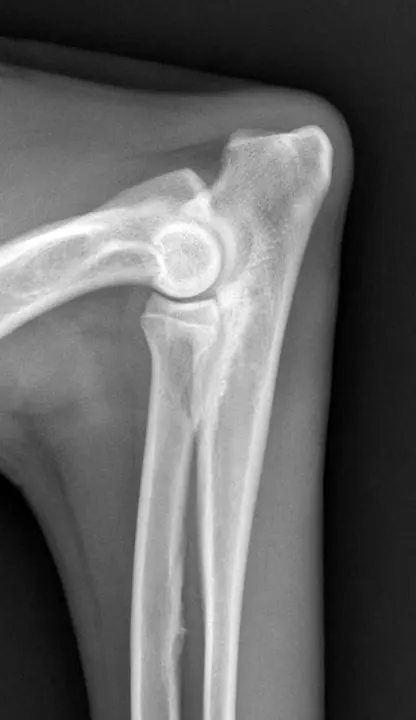

Following examination, Maggie was sedated with dexmedetomidine (3 μg/kg IM) and butorphanol (0.1 mg/kg IM), and orthogonal radiographs of both elbows were obtained. The left elbow appeared radiographically normal on the lateral view, whereas the right elbow had mild subtrochlear sclerosis subjacent to the trochlear notch and apparent loss of detail of the coronoid process (Figure 1). No abnormalities were detected on the craniocaudal view (Figure 2).

Because Maggie’s injury was acute and she had no historic, radiographic, or physical signs of chronicity, a traumatic fragmented medial coronoid process (TFMCP) was suspected as the cause of elbow effusion and pain. Because CT imaging provides excellent visualization of medial coronoid pathology and correlates well with arthroscopic findings,2 a CT scan of both elbows was offered before surgery for further diagnostic evaluation but was declined by the owner due to financial constraints. Thus, arthroscopy was elected as a single diagnostic and potentially therapeutic approach to reduce the overall cost of the treatment plan.